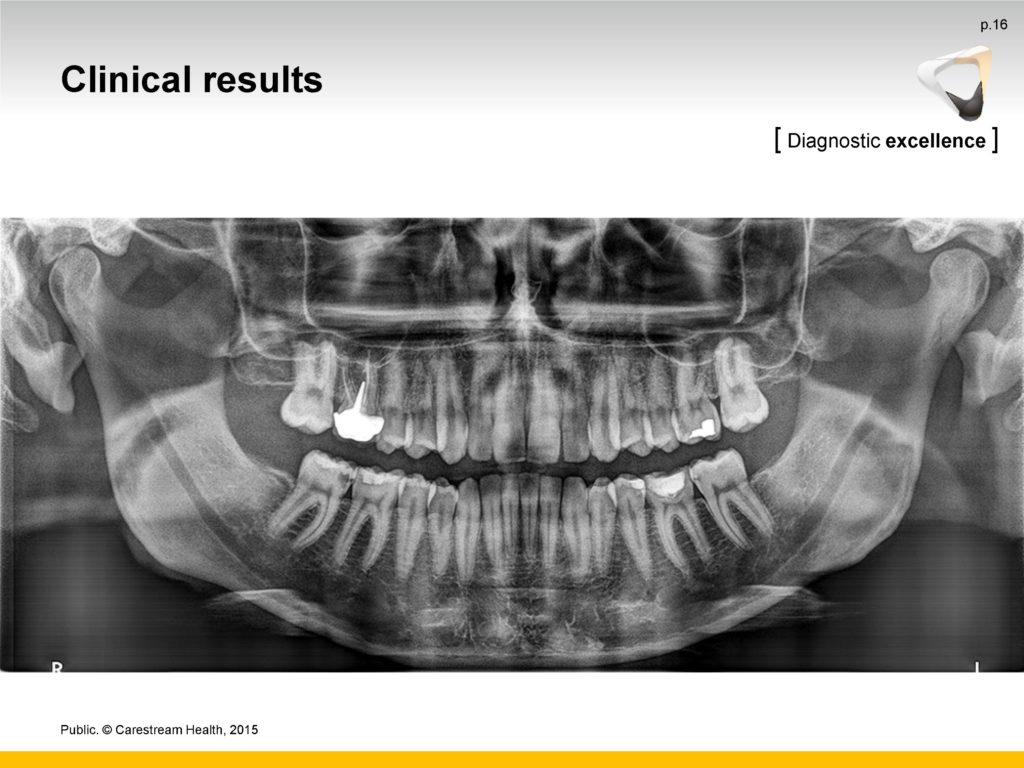

- Uz najnovije algoritme za obradu softvera, CS 8100 minimizira sjene kralježnice i proizvodi jasne, oštre digitalne slike koje su spremne za pregled gotovo odmah.

- Napredni Active Pixel CMOS senzor, sustav za kretanje bez vibracija i 0,5 žarišne točke osiguravaju detaljne, kontrastne, kristalno jasne slike u sekundi

- Snažni filtri bez artefakata povećavaju kontrast i oštrinu jednim klikom